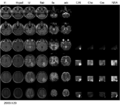

To segment all MR image volumes available for a patient we developed an approach for learning patient-specific lesion atlases with limited user interaction. Figure 1 shows the manual segmentations of the tumor from different raters (red, green, blue) and the automatic segmentation using a patient-specific lesion atlas (black) in T1-MRI, T1-MRI and the fractional anisotropy map from DTI. The right image shows the lesion atlas.